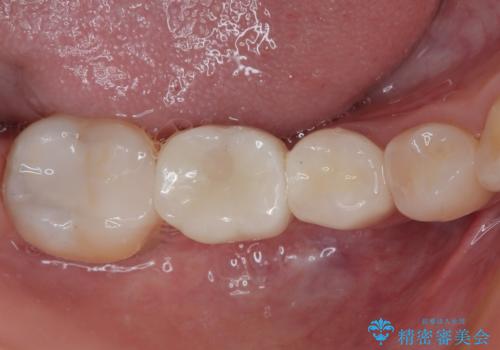

- 以前他院で治療を行った前歯の被せものが欠けてしまい、きれいなセラミックにしたいと来院された患者様です。

人工物のような印象が強くあまり自然とは言えない状態でした。

また被せものと土台の間に隙間があり、適合もよくない状態でした。

根管治療のやり直しは希望されなかったため、土台のやり替えと、より自然なオールセラミッククラウンへのやり替えを行いました。

自然できれなオールセラミッククラウンになり、とても満足されました。